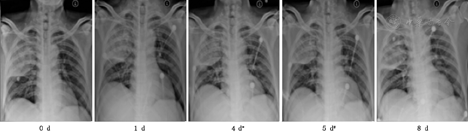

由疾控中心专业人员采样留取两份呼吸道标本(鼻咽分泌物及深部痰)作病毒核酸检测,雾化治疗后1~4 d,4例患者第1次病毒核酸检测转阴,分别间隔24 h以上再次阴性后解除隔离,详见表2。治疗后患者咳嗽、咳痰、胸闷等呼吸道症状及发热等症状逐渐好转,详见表3。呼吸频率、血常规及血气分析均恢复正常,详见表4。复查胸部影像X线检查,肺部原发病灶均逐渐吸收好转,均无新发病灶,详见图1,图2,图3,图4。

注:*表示第一次咽试子及深部痰病毒核酸检测转阴,#表示第二次咽试子及深部痰病毒核酸检测转阴(以下相同)